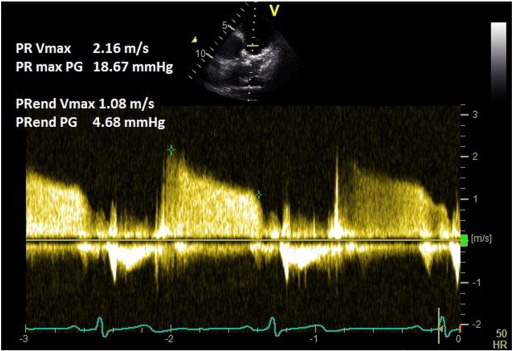

A pulmonary regurgitation (PR) signal is obtained in the parasternal short axis view using colour Doppler. CW Doppler at a sweep speed of 100 mm/s is used to measure the peak PR velocity (Fig. 3 ). Peak pressure difference (measured by the Bernoulli equation) is then added to the RAP. This method has been validated against gold standard catheter-measurements [13] and [14] . Mean PAP can be approximated from the peak PR Doppler signal using the following formula: mPAP = 4(PRpeak velocity)2 + RAP.

Fig. 3. Pulmonary regurgitation method for measuring mean and diastolic pulmonary artery pressure. |

The PR signal may be poor or parallel alignment of the Doppler signal may not be possible. In the presence of constrictive or restrictive RV physiology, PR Doppler signals could provide a valuable clue towards the diagnosis but may be unreliable in the calculation of pulmonary artery pressure [15] . In constrictive physiology, there is dissociation of intracardiac from intrathoracic pressure, resulting in early equalisation of PA and RV pressures with inspiration. This results in shorter and steeper PR signal [16] .

A PR signal is obtained as above. End PR velocity is measured in multiple (non-continuous) traces and averaged. Pulmonary artery diastolic pressure (PADP) is calculated from the following equation: 4(PR-end velocity)2 + RAP. Mean pulmonary artery pressure can be calculated from systolic (by TRmax method) and diastolic (by PR-end velocity method) pulmonary artery pressures:

In severe pulmonary regurgitation, due to a rapid deceleration slope, PR-end velocity may underestimate the pulmonary artery diastolic pressure [14] . As mentioned earlier, this technique may not be useful in the presence constrictive or restrictive physiology [15] and [16] .